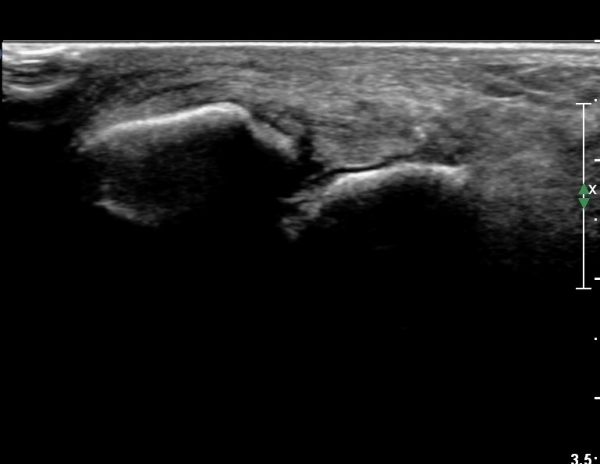

Àü¹æ¸»´ÜÁ¾°ñºñ°ñÀδë Á¾´Ü¸é°Ë»ç¿¡¼­ ƯÀÌ ¼Ò°ßÀ» º¸ÀÌÁö ¾ÊÀ½(»çÁø 1).

Àü°ÅºñÀδë Á¾´Ü¸é°Ë»ç¿¡¼­  Àü°ÅºñÀδëÀÇ ÆÄ¿­À» º¸ÀÓ(»çÁø 2).